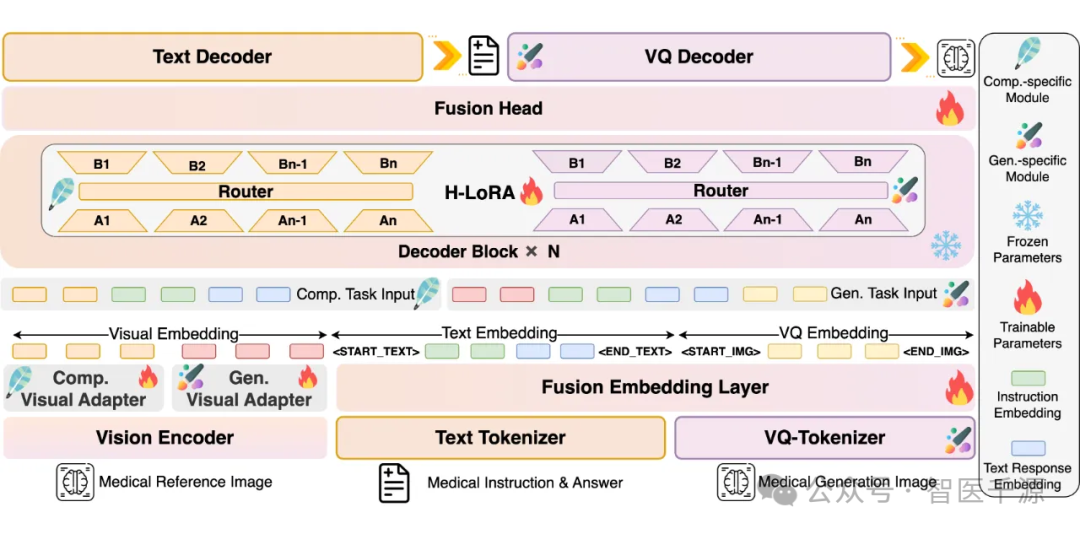

异构知识整合:通过自回归方法将文本与图像处理无缝融合,实现跨模态医疗场景应用。

创新架构:基于大语言模型(LLM)扩展,结合视觉编码器和生成器,提升医疗图像分析与合成的精度。